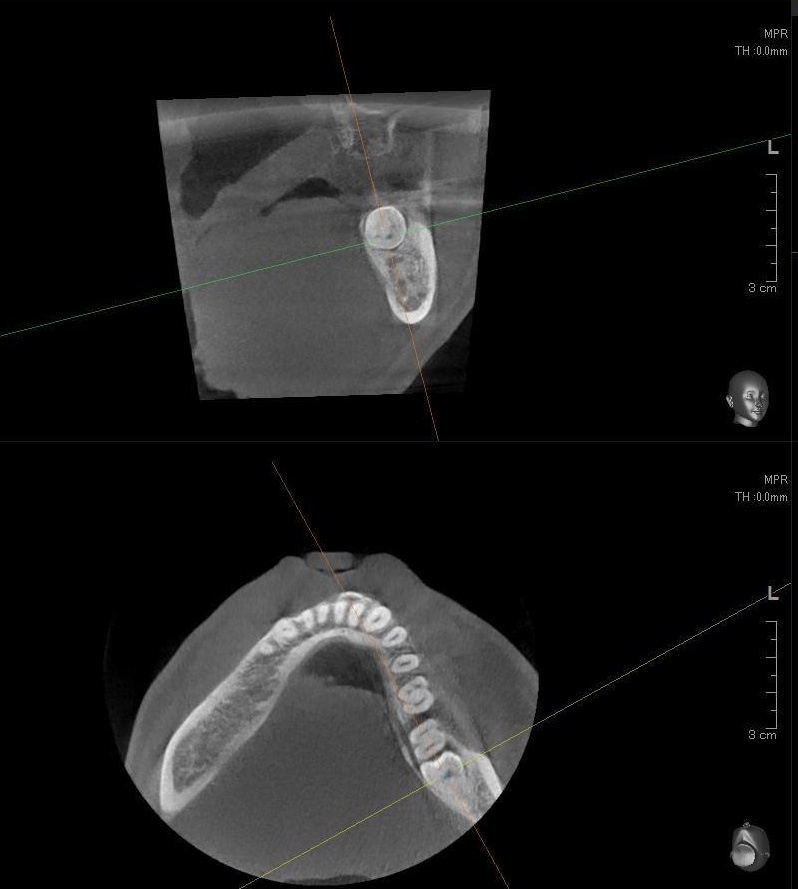

さらに、下顎の親知らずは下歯槽神経に非常に近いところに生えている場合もあるため、CTも撮影し詳しい解析を行います。

親知らずが生えている位置が、神経に近い、あるいは神経に当たっている場合は、大きな病院に紹介する場合もあります。

親知らずの根っこは下歯槽神経からは近い位置にありましたが、抜歯は可能と診断されました。